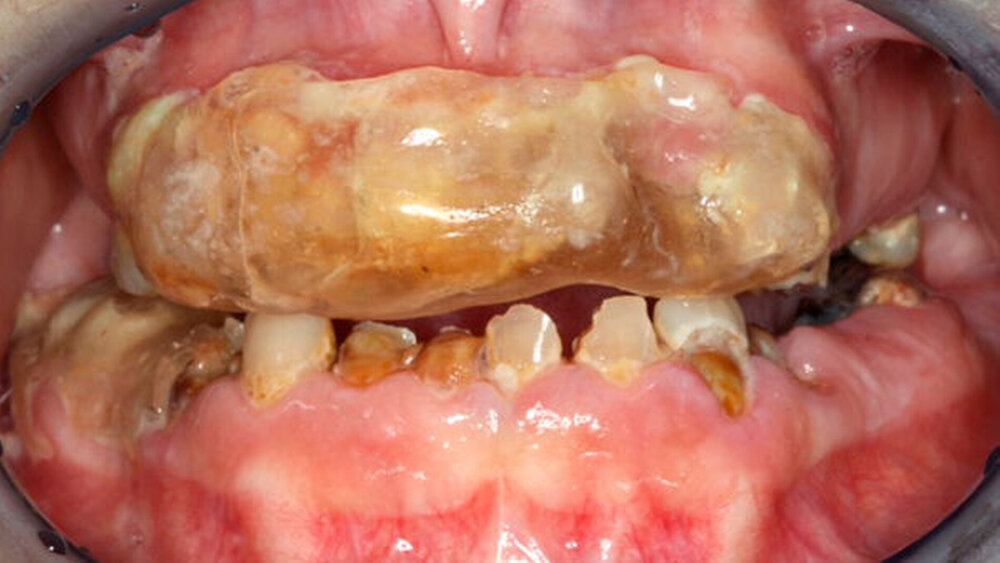

Bei der Inspektion der Mundhöhle fielen multiple kariöse Zähne beziehungsweise Wurzelreste sowie die massive „Schiene“ des Oberkiefers und Reste der „Unterkiefer-Schiene“ im vierten Quadranten auf. Nachdem ein Röntgenbild angefertigt worden war, wurde am Zahn 44 eine symptomatische Parodontitis apicalis diagnostiziert. Trotz massiver Zahnarztangst konnte die Patientin überzeugt werden, sich zeitnah einer umfassenden zahnärztlichen Behandlung zu unterziehen.

Leider konnte nach Entfernung des Kunststoffs und des darunter befindlichen Zahnsteins kein Zahn als erhaltungswürdig eingestuft werden, so dass nach Extraktion aller Zähne die Patientin nun mit Totalprothesen versorgt wird.